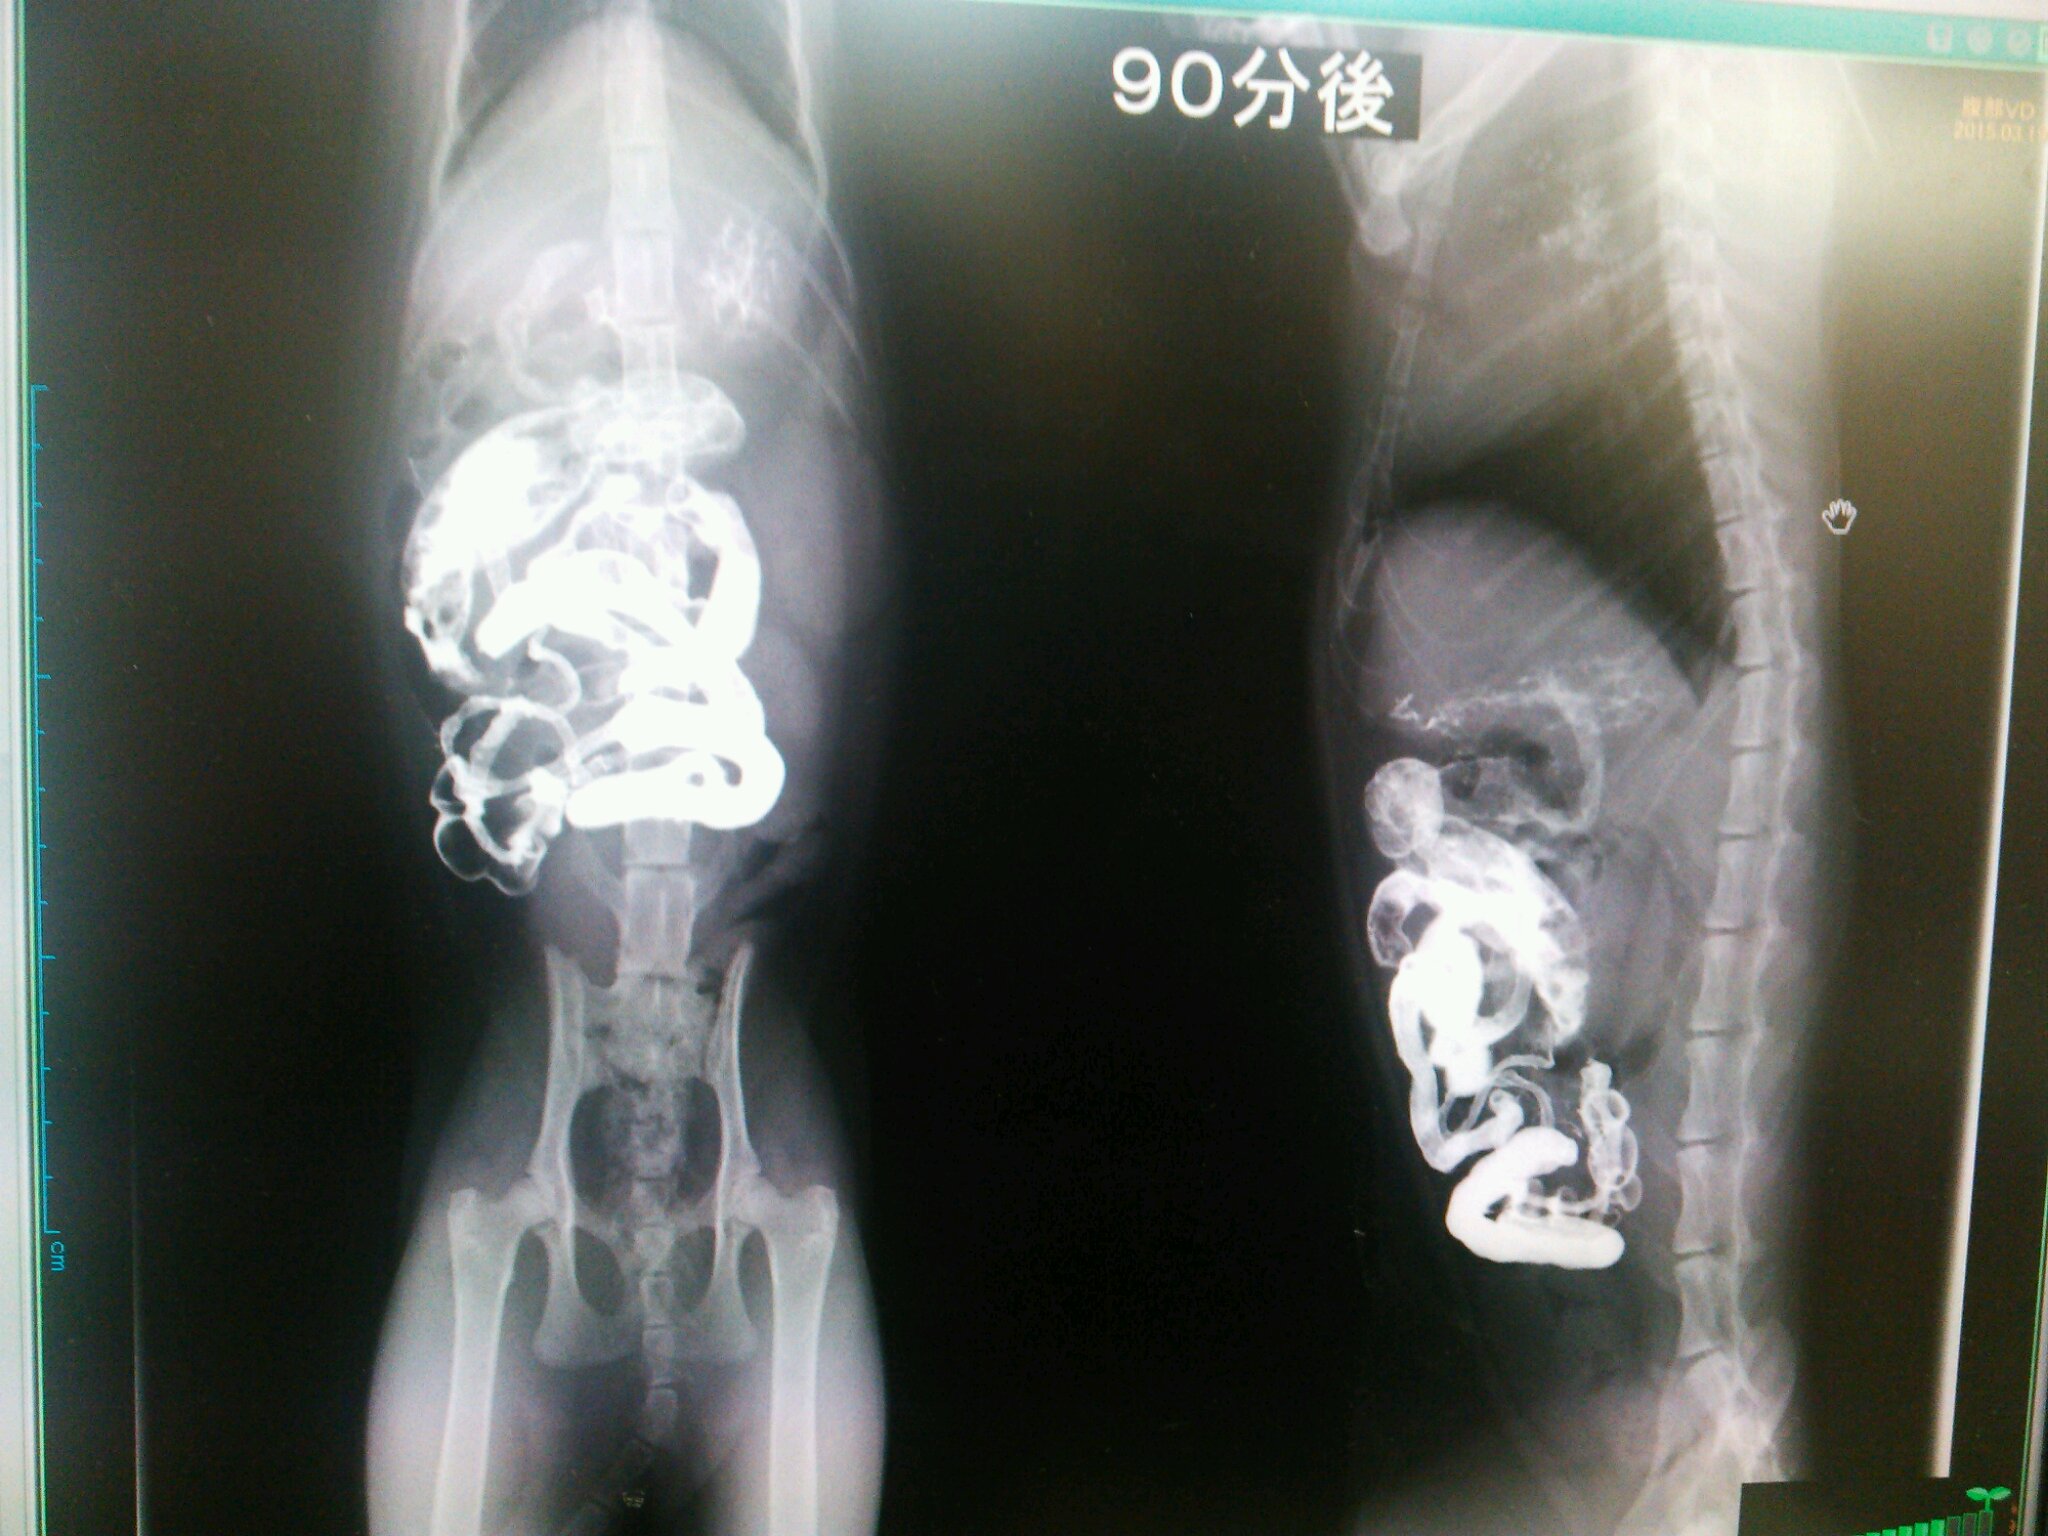

こんなカンジでバリウムが流れていって

どっかで止まれば、そこが腸閉塞っつー話でやんすた。

こんなことを5時間以上続けたらしい。